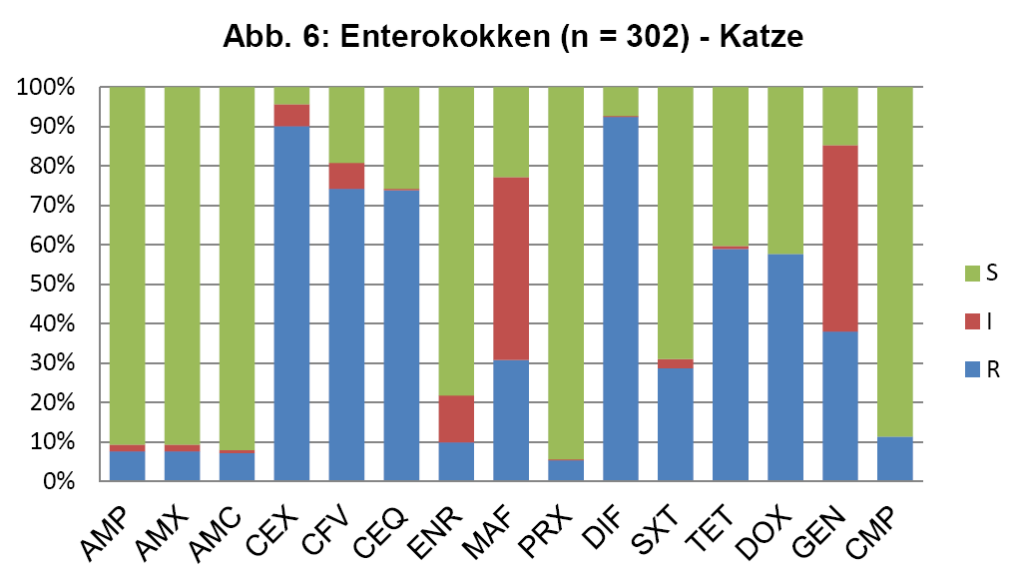

- Abb. 6: Enterokokken (n = 302) – Katze

Die vier wichtigsten Keime bei der Katze sind E. coli, Staphylokokken (koagulasepositive und -negative) und Enterokokken. Diese machen zusammen sogar 77% der Nachweise aus. Um nun zu überprüfen, ob die in den ISCAID Richtlinien vorgeschlagenen Wirkstoffe für eine empirisch ausgesuchte Ersttherapie auch für unsere Verhältnisse Gültigkeit haben, muss man die Resistenzmuster dieser Keime einzeln überprüfen. Die Darstellung dieser Daten würde den Umfang eines LABOKLIN aktuell sprengen. Daher geben wir hier exemplarisch die wichtigsten Keime wieder. Abb. 4 zeigt die Resistenzverteilung von E. coli bei HWI vom Hund, die Verhältnisse bei der Katze sind ähnlich.

Abb. 5 zeigt die koagulasepositiven Staphylokokken vom Hund, die Daten für die koagulasenegativen Staphylokokken der Katze sind ähnlich. Die seltener bei der Katze nachgewiesenen koaglulasepositiven Staphylokokken sind etwas resistenter. Abb. 6 zeigt die Enterokokken bei der Katze.

Für die Ersttherapie werden nach ISCAID Richtlinien AMX und SXT vorgeschlagen, wobei AMX der Vorzug gegeben wird. In vielen europäischen Ländern ist AMX sehr gut wirksam gegen E. coli. Dies ist offensichtlich bei uns nicht der Fall (s. Abb. 4). Bei unklarer Keimzusammensetzung wäre daher SXT nach unserer Datenlage für die Ersttherapie der Vorzug zu geben. Auf ENR sollte zunächst aus den oben genannten Gründen verzichtet werden. Es wird noch als Reserveantibiotikum für wirklich schwierige Infektionen benötigt. Wenn im Harnsediment eine Unterscheidung in Kokken und Stäbchen erfolgt, kann man bei Vorliegen von Kokken gut mit AMX als Ersttherapie arbeiten (s. Abb. 5 + 6). Es muss bedacht werden, dass die uns vorliegenden Daten die eigentliche Resistenzlage zu hoch wiedergeben könnten, da häufig erst bei Therapieversagen eine BU eingeleitet wird. Somit könnte die Resistenzlage für AMX in der Praxis besser sein, als hier dargestellt. Darüber hinaus reichert sich AMX im Urin stark an.